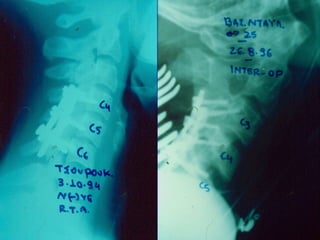

FFaacceett ffrraaccttuurreess aanndd

DDiissllooccaattiioonnss

BBiioommeecchhaanniiccss eettiioollooggyy

–FFlleexxiioonn ddiissttrraaccttiioonn wwiitthh oorr wwiitthhoouutt

llaatteerraall fflleexxiioonn aanndd rroottaattiioonn..

–MMaajjoorriittyy aarree MMVVAA wwiitthh CC55--66,, CC66--77

mmoosstt ccoommmmoonn lleevveell..

–5500%% ooff iinnjjuurreedd hhaavvee aassssoocciiaatteedd

ffaacceett ffrraaccttuurreess